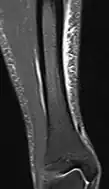

Musculoesquelético

As aplicações no sistema músculo-esquelético incluem imagens espinhais, avaliação de doenças das articulações e tumores de tecidos moles.[44]

| Recuperação de inversão | Inversão de tau curto | STIR | Supressão de gordura, definindo um tempo de inversão onde o sinal da gordura é zero. | Sinal alto em casos de edema, como em fraturas por estresse mais graves.[71] Canelite, por exemplo. | ![]() |